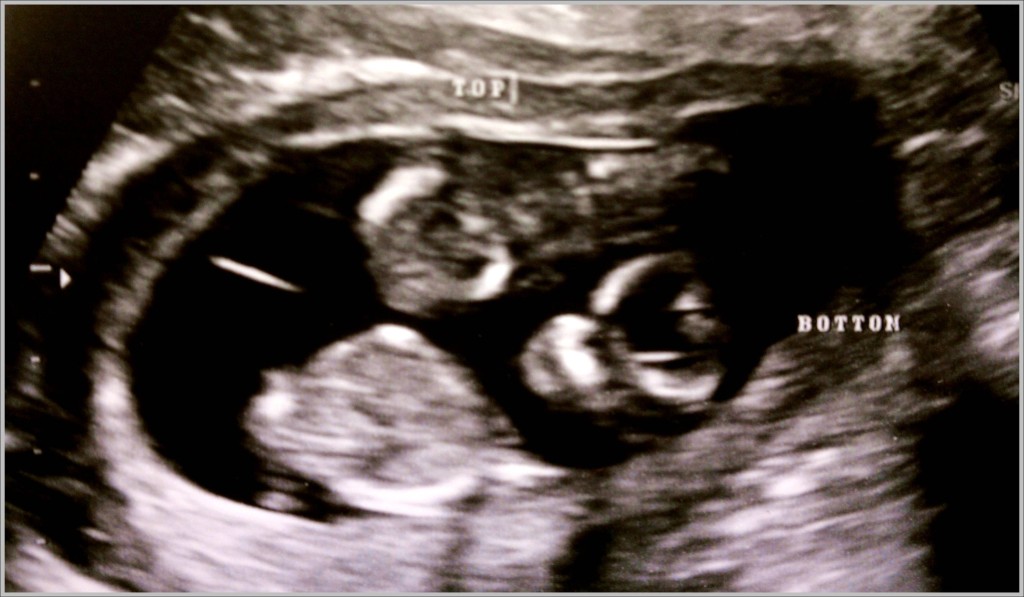

Twins 6 week ultrasound! Ohh I pray I have identical twin girls one day

Twins 6 week ultrasound! Ohh I pray I have identical twin girls one day What Do Identical Twins Look Like On Ultrasound however, identical (monozygotic) twins might share an amniotic sac or have separate sacs depending on. It depends on how much detail your sonographer can see and whether or not your twins share a placenta. The sizes of the babies. what about with twins? There are a few variations of identical twins: It's important to attend this. At this. What Do Identical Twins Look Like On Ultrasound.